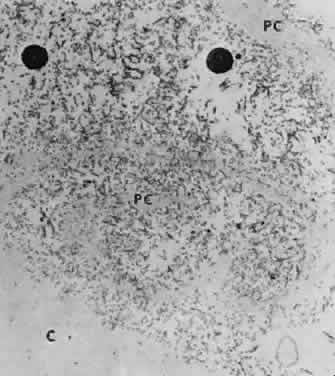

Accumulation of exfoliative material may be detected histopathologically throughout the anterior segment to include the lens, iris, trabecular structures, conjunctiva, ciliary body, and zonules. The deposition of fibrillar eosinophilic material on the anterior lens capsule is the classic histopathologic feature of XFS (Fig. 9). Ultrastructural studies also indicate some degree of actual exfoliative changes or peeling of the anterior lens capsule74 (Figs. 10 and 11). In addition, Ashton and associates describe a degenerative band containing exfoliative material within the inner half of the lens capsule.5 Bertelsen and coworkers independently noted projection of coarse fibrils from the lens surface into the deep portion of the lens capsule to form an amorphous layer of the lens capsule between the lens epithelium and normal lens capsule.6 Thus, studies indicate that exfoliative material accumulates on the anterior lens surface but also that the lens capsule itself may be involved, and that the underlying epithelial layer may at least partially contribute to the production of the exfoliative material.

Fig. 10. Scanning electron micrograph showing layer of anterior lens capsule and exfoliative material (PC) peeling back from rest of capsule. Asterisks indicate exfoliative vegetations (× 5340). (Dark AJ, Streeten BW, Cornwall CC: Pseudoexfoliative disease of the lens: A study in electron microscopy and histochemistry. Br J Ophthalmol 61:466,1977)

Fig. 11. Transmission electron micrograph of peeling lens capsule (PC) rolled up in spiral, enclosing masses of exfoliative fibers and two melanin granules. C, main capsule (× 14,600). (Courtesy of Dr. Barbara Streeten)